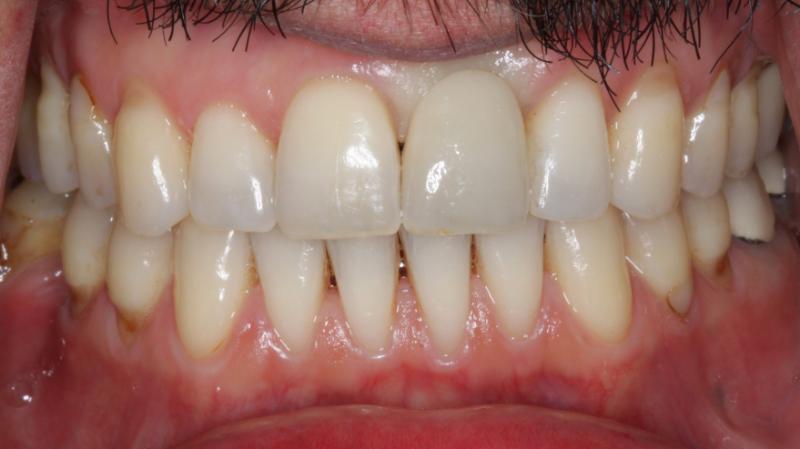

A dental implant is a small titanium post that is surgically placed into the jawbone, providing a foundation for a replacement tooth or teeth. Placing an implant is a common surgical procedure performed by our highly trained prosthodontist.

Dental implants offer incredible benefits, including improved oral health, increased confidence, and better functionality and comfort when compared to traditional dentures or bridges.

If you have one or more missing teeth or are experiencing problems with your dentures, our Reston dental implants may be a great option for you. We don’t take a one-size-fits-all approach and would love to see you for a consultation and give you a personalized evaluation and recommendation.